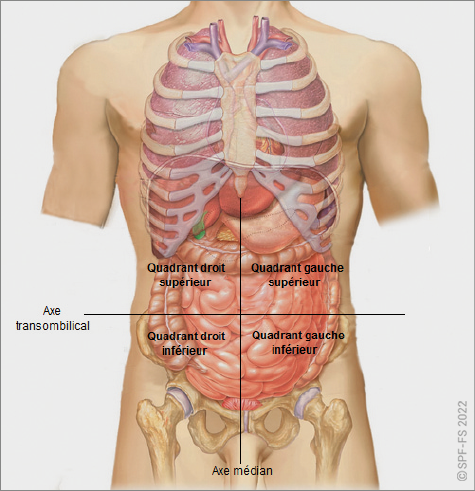

4. Les cavités

Il existe quatre cavités :